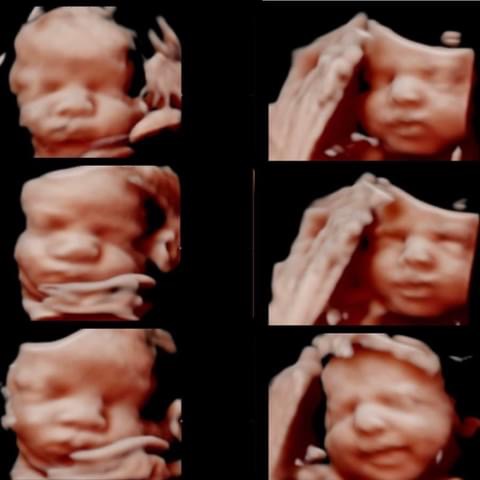

All photos are from our equipment and are of our actual clients.